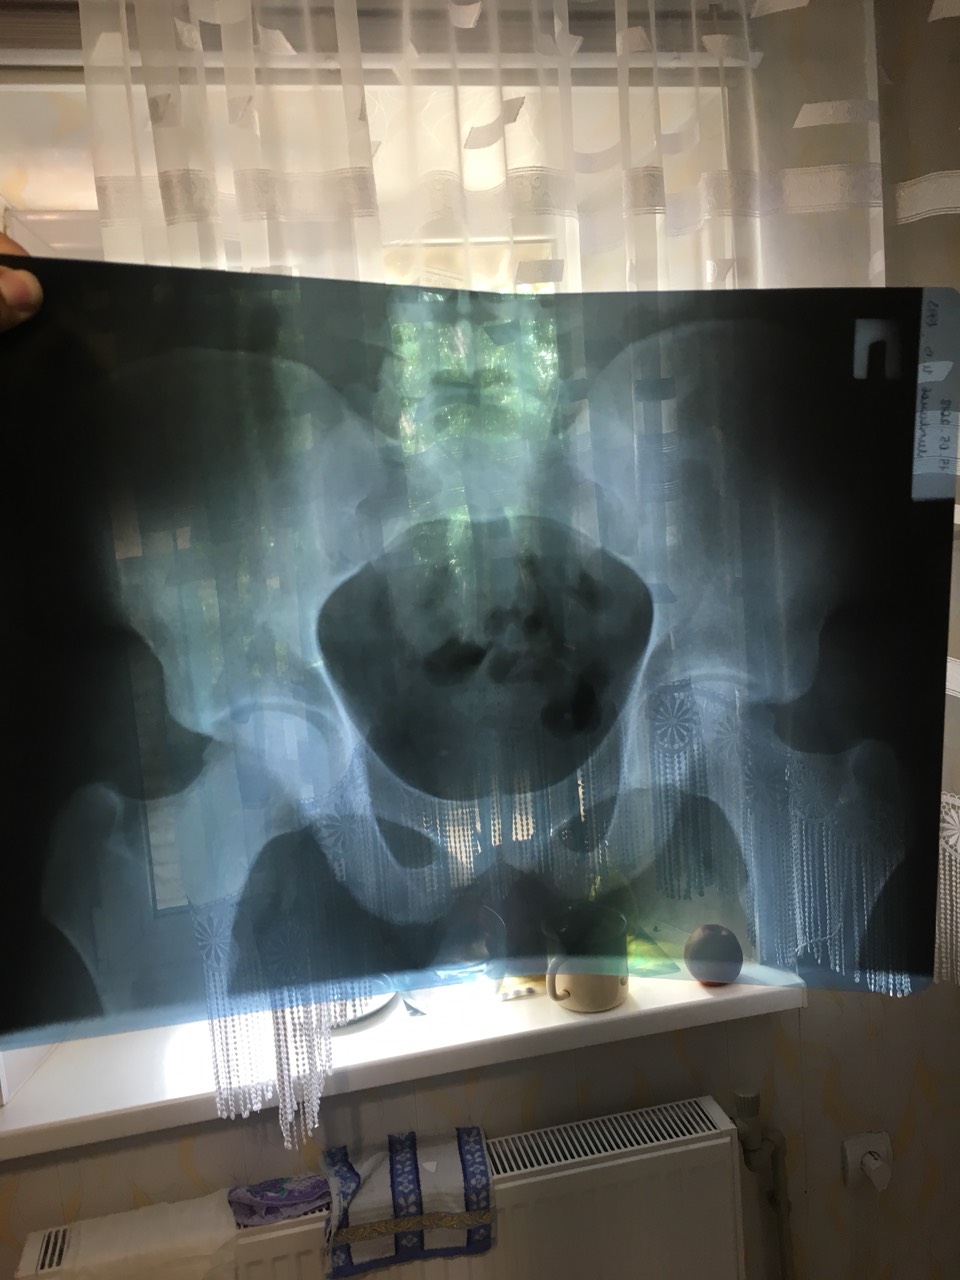

К тому же эрозии, которые являются практически однозначным признаком сакроилеита на рентгенограммах видны обычно плохо и редко, поэтому диагноз часто ставят на рентгенологических признаках скорее артроза этих суставов. Поэтому, если выраженных эрозий на рентгенограммах нет, то нужно сделать МРТ, чтоб определить, есть ли там воспаление. Если явного воспаления нет (МРТ это обычно хорошо видит), то диагноз сакроилеита (а следовательно и Бехтерева следует очень внимательно пересмотреть еще раз). Ну и ревмопробы сдать (СРБ, РФ, АСЛО) + общий анализ крови (интересует СОЭ) + специфический антиген для болезни Бехтерева (HLA-B27) - наличие последнего, хоть и не 100% признак заболевания, но очень веский признак наследственной склонности, поэтому он очень и очень сильно помогает уточнить диагноз. Без этого всего диагностировать болезнь Бехтерева очень проблематично. Конечно, когда уже на снимках позвонки посрастались, тогда можно ставить диагноз и без анализов, но это уже достаточно запущенная стадия, а желательно определяться с диагнозом, а следовательно и лечением, пораньше.

По ее словам рентген лучше видет двухсторонний сакроилет ,на счет мрт,самый мощный который есть 1.5 тесла(много или мало не знаю)

Часть анализов пришла

Вот тебе мои "бумажки":

Первое обследование.

Второе обследование.